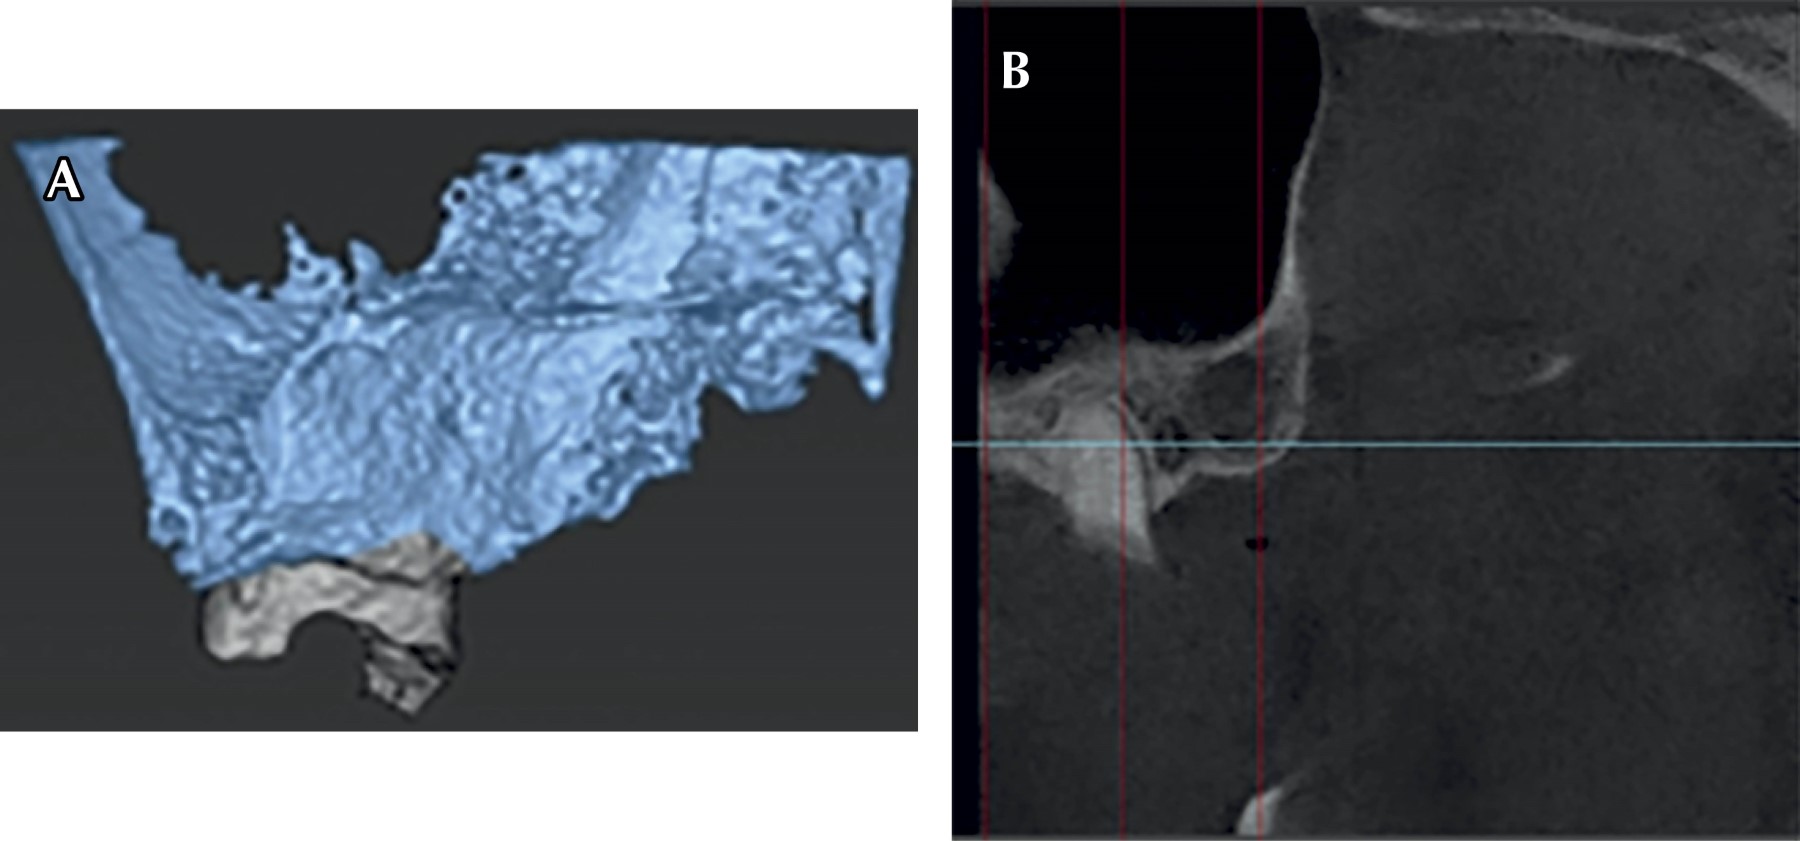

Bisphosphonates are synthetic analogue drugs of pyrophosphates that have a high antiresorptive potency in the bone remodeling cycle. They have in their chemical structure a carbon atom which remains linked to two phosphate groups (P-C-P), their negative charge explains the affinity they have for bone tissue. This clinical report presents the treatment of a patient with a history of osteoporosis, who, due to the use of removable partial dentures in poor condition, caused severe atrophy of the alveolar ridge. Currently, he is prescribed zoledronic acid (bisphosphonates). The placement of dental implants and extractions is contraindicated in patients on bisphosphonate treatment, so an alternative treatment is chosen that consists of a removable polyoxymethylene partial prosthesis and a four-unit bridge with an endocrown-type posterior abutment design. After one year, with 11 months of use of the new fixed prosthesis, the patient did not present dislodgement of the bridge, no occlusal problem was observed, with no absence of increase in the resorption of the edentulous alveolar ridge in the maxilla and mandible, the treatment gave great results both for the general health of the patient and to meet her expectations.

Figure 2